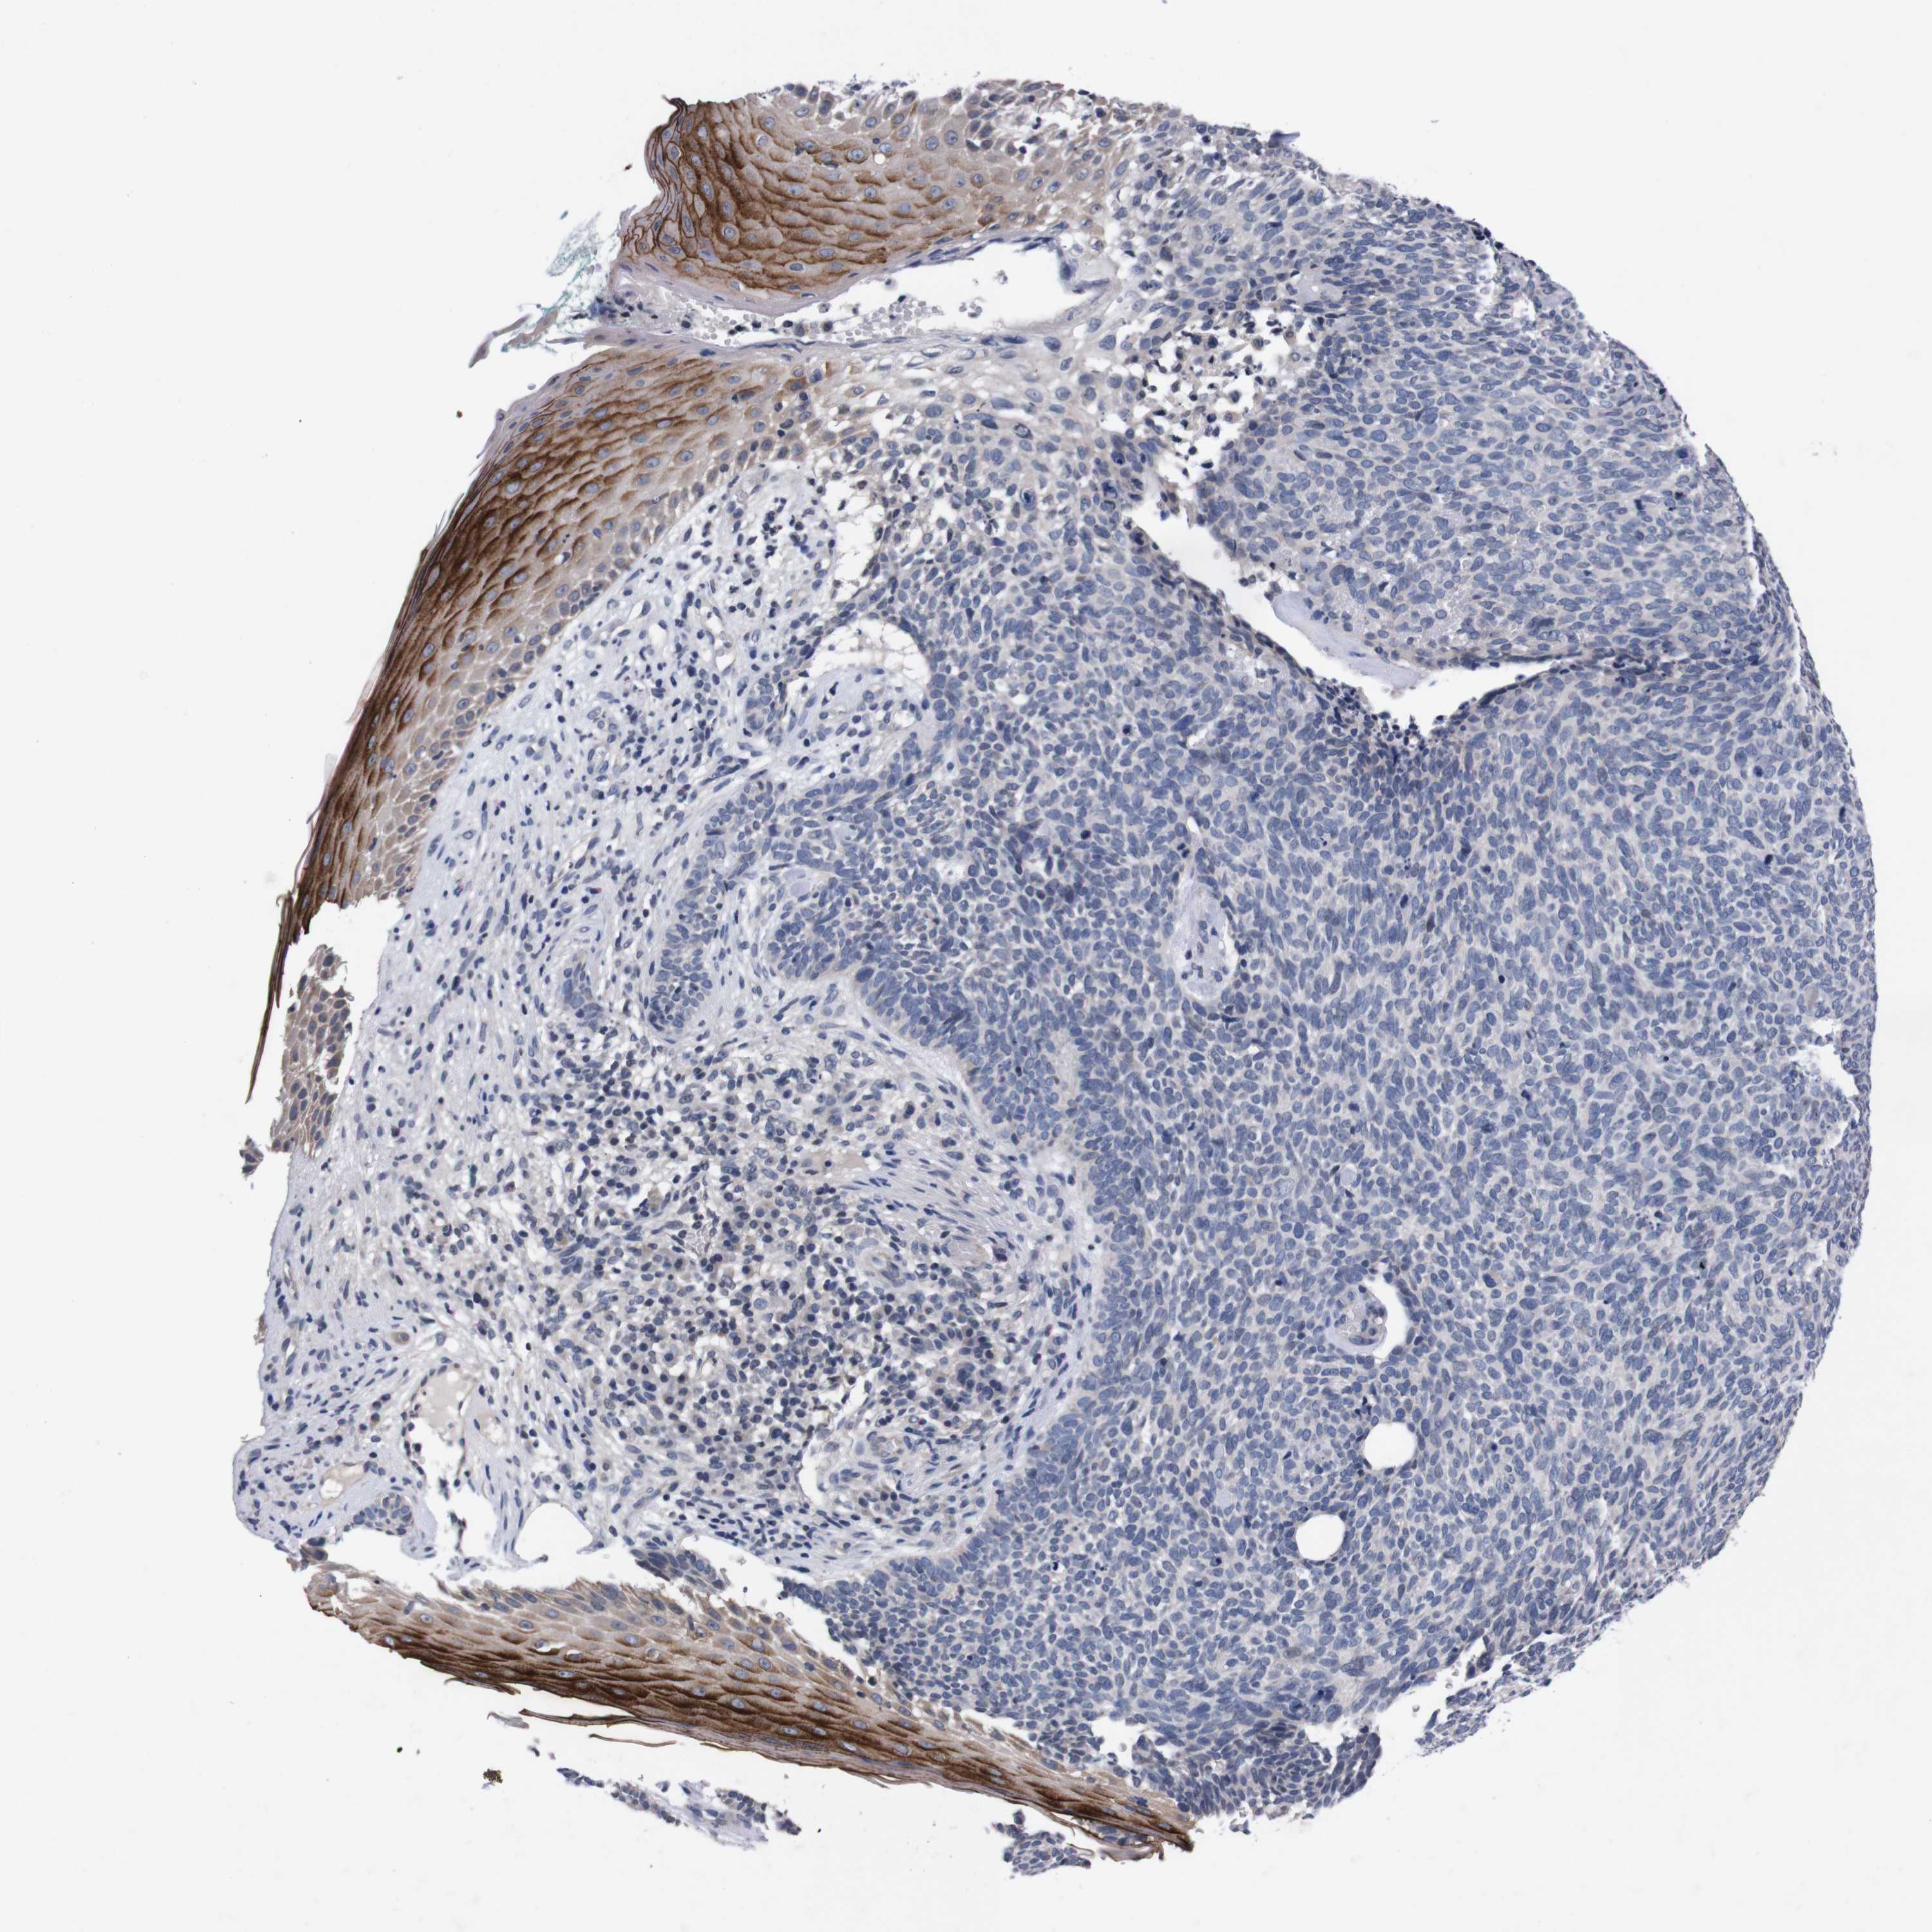

SKIN CANCER - Protein expressioni

A mouse-over function shows sample information and annotation data. Click on an image to view it in a full screen mode. Samples can be filtered based on level of antibody staining by selecting one or several of the following categories: high, medium, low and not detected. The assay and annotation is described here.

Antibody stainingi

Antibody staining in the annotated cell types in the current human tissue is reported as not detected, low, medium, or high, based on conventional immunohistochemistry profiling in selected tissues. This score is based on the combination of the staining intensity and fraction of stained cells.

Each image is clickable and will lead to virtual microscopy that enables deeper exploration of all samples and also displays staining intensity scores, fraction scores and subcellular localization as well as patient and tissue information for each sample.

Antibody HPA006746

Antibody CAB009805

Squamous cell carcinoma, NOS

Squamous cell carcinoma, metastatic, NOS